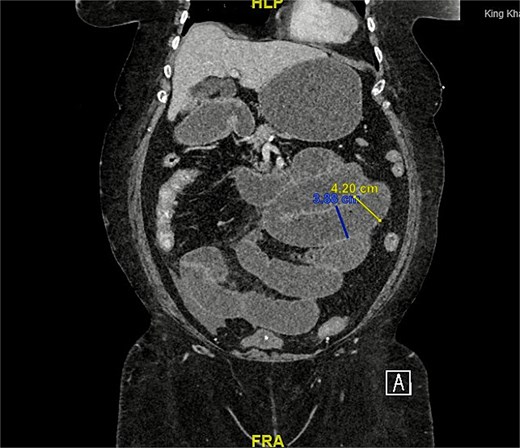

A computed tomography (CT) scan of the abdomen and pelvis was performed for further evaluation. The coronal view demonstrated a markedly distended stomach, mesenteric fat stranding with a small amount of free fluid, along with bowel dilation involving the mid and proximal small bowel loops (measuring up to 4 cm) with a transition zone at the site of bowel twisting over the suprapubic catheter (Fig. 1). On the sagittal view, the suprapubic catheter was seen positioned correctly within the bladder (Fig. 2). The bowel demonstrated normal enhancement, with no evidence of wall thickening, pneumatosis intestinalis, or pneumoperitoneum.

CT scan coronal view: Demonstrating distended small bowel loops consistent with small bowel obstruction, with a transitional zone at the twist of bowel over the suprapubic catheter.